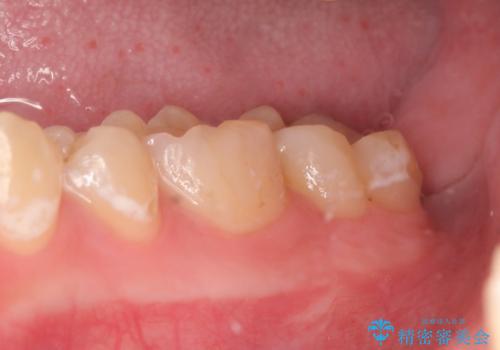

術後歯肉の回復を待ち、左下6はセラミックインレー、左下7はオールセラミッククラウンにて補綴しました。

当院のセラミックインレーはemaxという強度と審美性に優れた材料を使用しています。

またプレス方式でインレーを製作しているため、削り出しで製作するCADCAMより優れた適合性も持ち合わせており、虫歯が再発しにくい修復物です。

オールセラミッククラウンについて

オールセラミッククラウン(エコノミー)はスタンダード以上と違い、一塊となっているため欠けてしまうリスクが低いのが特徴です。

しかしその反面選択できる色の種類が少なく、色合いも単調であるという欠点もありますが、今回のケースのように前後の歯がクラウンの場合などでは十分に審美的な補綴が可能となります。